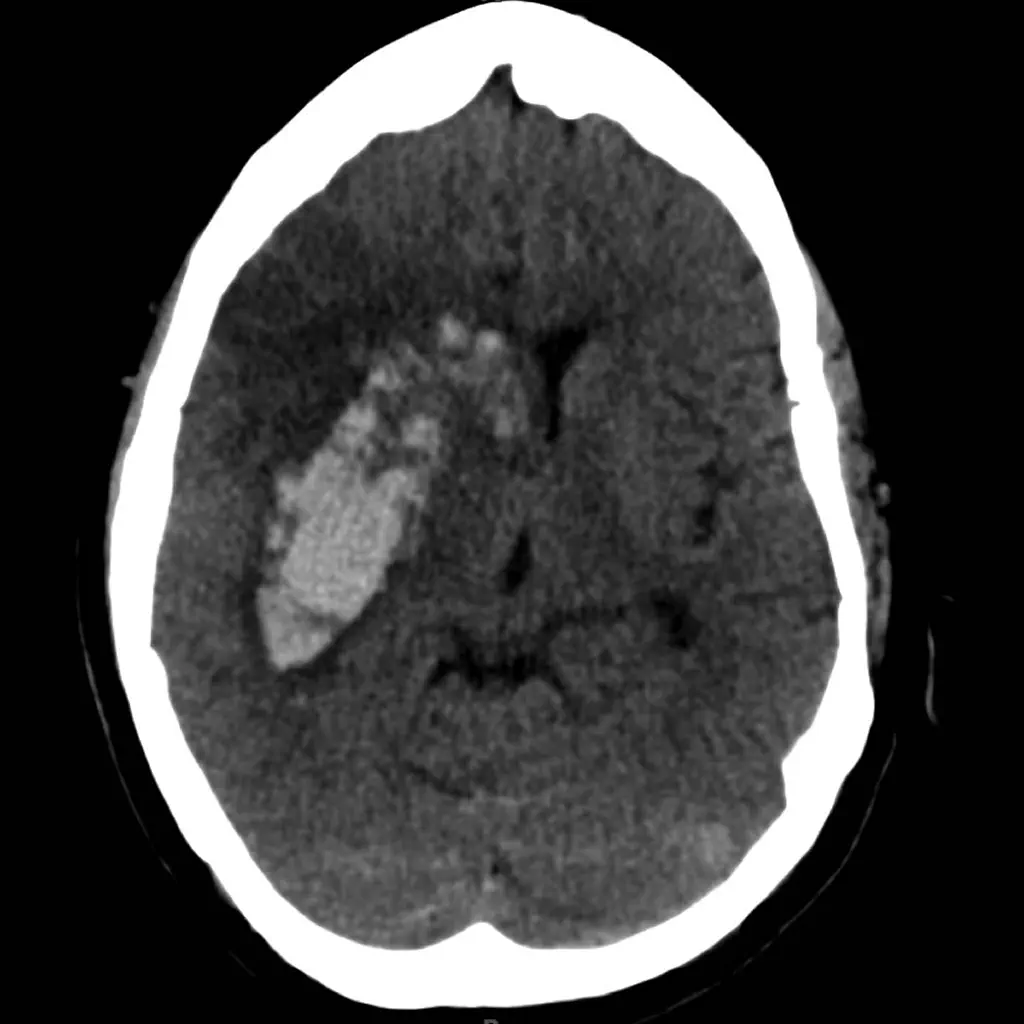

HeRS is a clinical calculator designed for rapid risk stratification. The system quantifies the probability of hemorrhagic transformation in patients with acute ischemic stroke who have an indication for anticoagulation. The interface captures continuous variables for patient age, renal function (eGFR), and infarct volume. It then leverages a complex, prospectively validated regression equation to compute the HeRS score, delivering a precise risk assessment in seconds to circumvent the difficulty of manual calculation in a clinical setting.

- The score's core variables were derived from a retrospective analysis (N=123) that identified age, infarct volume, and eGFR as significant, independent predictors of hemorrhagic events in this patient population.

- Initial research noted that while anticoagulation did not significantly increase overall hemorrhage rates, all observed intracerebral hematomas and symptomatic hemorrhages occurred within the anticoagulated patient group.